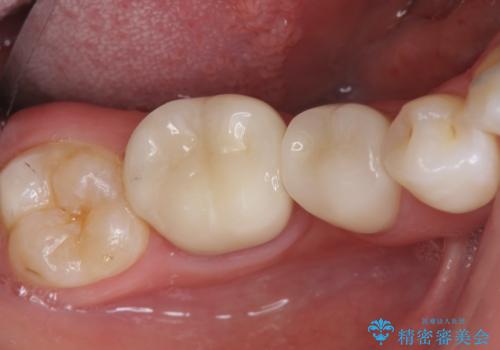

色調の自然さや、噛み合わせが改善され、満足いただくことができました。

- 26.4万円(ジルコニアクラウン×2・仮歯×2)費用は治療当時の料金となります